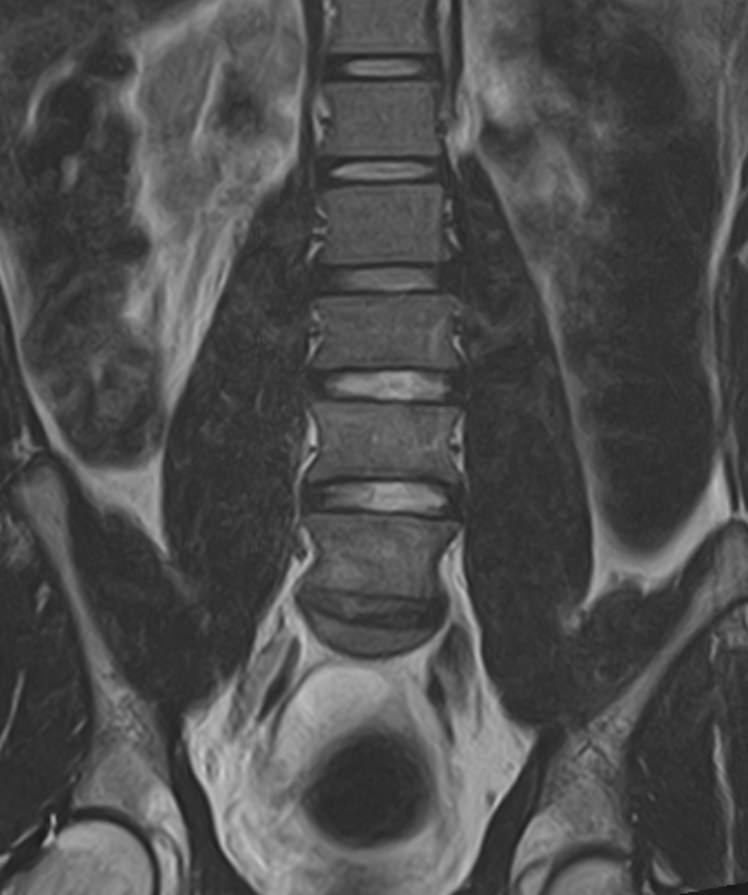

Наиболее точным и эффективным способом диагностики причин появления болей в нижней части спины является МРТ пояснично-крестцового отдела позвоночника. С помощью данного метода можно оценить состояние всех анатомических структур позвоночного столба на исследуемом уровне, безошибочно выявить происхождение болевого синдрома и назначить своевременное лечение.

Многим пациентам интересно, что показывает МРТ пояснично-крестцового отдела. Высокая детальность получаемых с помощью МР-диагностики изображений позволяет с точностью выявить следующие заболевания, локализующиеся в области поясничного отдела позвоночника:

• протрузии и грыжи межпозвонковых дисков;

• дегенеративные заболевания: остеохондроз, спондилез, спондилоартроз;

• последствия перенесенных травм, такие как компрессионные переломы, подвывихи и смещения позвонков;

• новообразования первичного и вторичного генеза;

воспалительные и деструктивные изменения позвонков и окружающих мягких тканей.